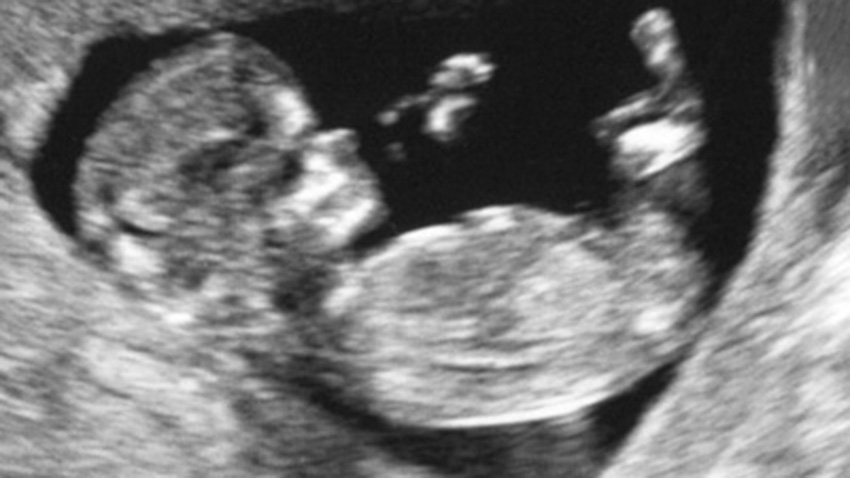

Ultraschall

Sie erwarten ein Kind und haben sich zur Schwangerschaftskontrolle angemeldet. Mit verschiedenen Methoden können wir heute beurteilen, ob alles in Ordnung ist oder ob Risiken vorliegen.